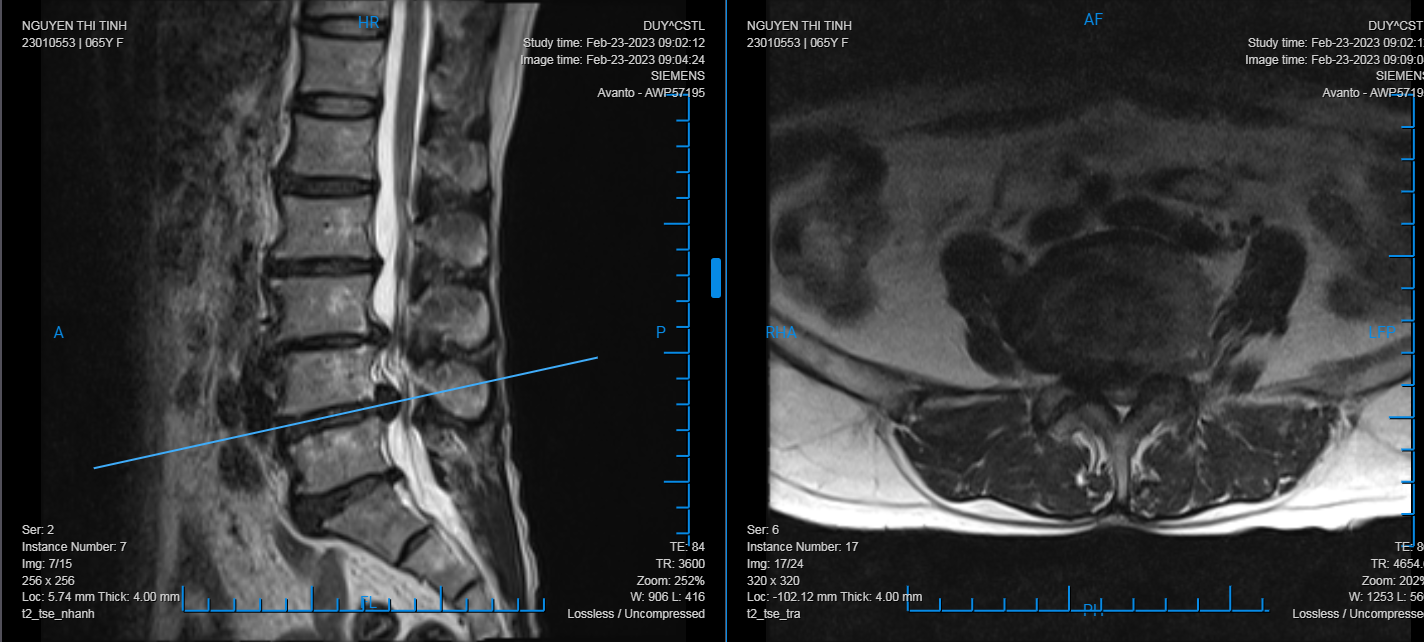

Qua thăm khám và các chỉ định cận lâm sàng cần thiết, bác sĩ Khoa Ngoại Chấn thương chỉnh hình chẩn đoán người bệnh bị thoát vị đĩa đệm L34, L45 gây hẹp nặng ống sống thắt lưng và chèn ép rễ thần kinh ngang mức. Bệnh nhân được chỉ định phẫu thuật cố định cột sống, giải ép thần kinh và hàn xương liên thân đốt L34, L45.

Ca phẫu thuật được tiến hành thuận lợi, sau phẫu thuật bệnh nhân hết triệu chứng đau nhức 2 chân và đã được hướng dẫn tập Phục hồi chức năng ngay sau mổ. Theo bác sĩ Nguyễn Mạnh Thuần – Khoa Ngoại chấn thương chỉnh hình, thoát vị đĩa đệm gây chèn ép rễ thần kinh, tủy sống thì phẫu thuật giải ép, ghép xương liên thân đốt và cố định cột sống là phẫu thuật triệt để và ổn định nhất cho người bệnh.